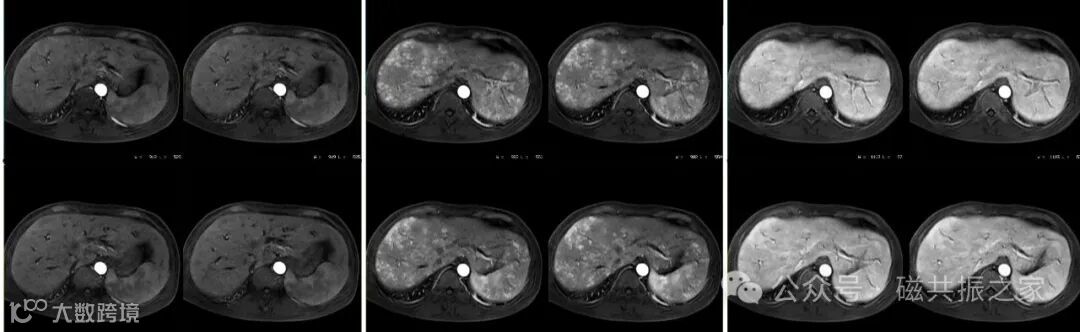

动脉期不均匀显著强化,门脉期以后均匀强化。

动脉期呈花斑样强化,门脉期以后呈均匀强化,上图△,分别为动脉早期,动脉晚期,门脉期图像。

动脉期呈花斑样强化是由于快速血流(小动脉血液直接进入静脉性血窦,90%)和慢速血流(小动脉血流经红髓迂曲纤维网状结构和白髓淋巴组织的边缘带后,再进入静脉血窦)共同作用的结果。